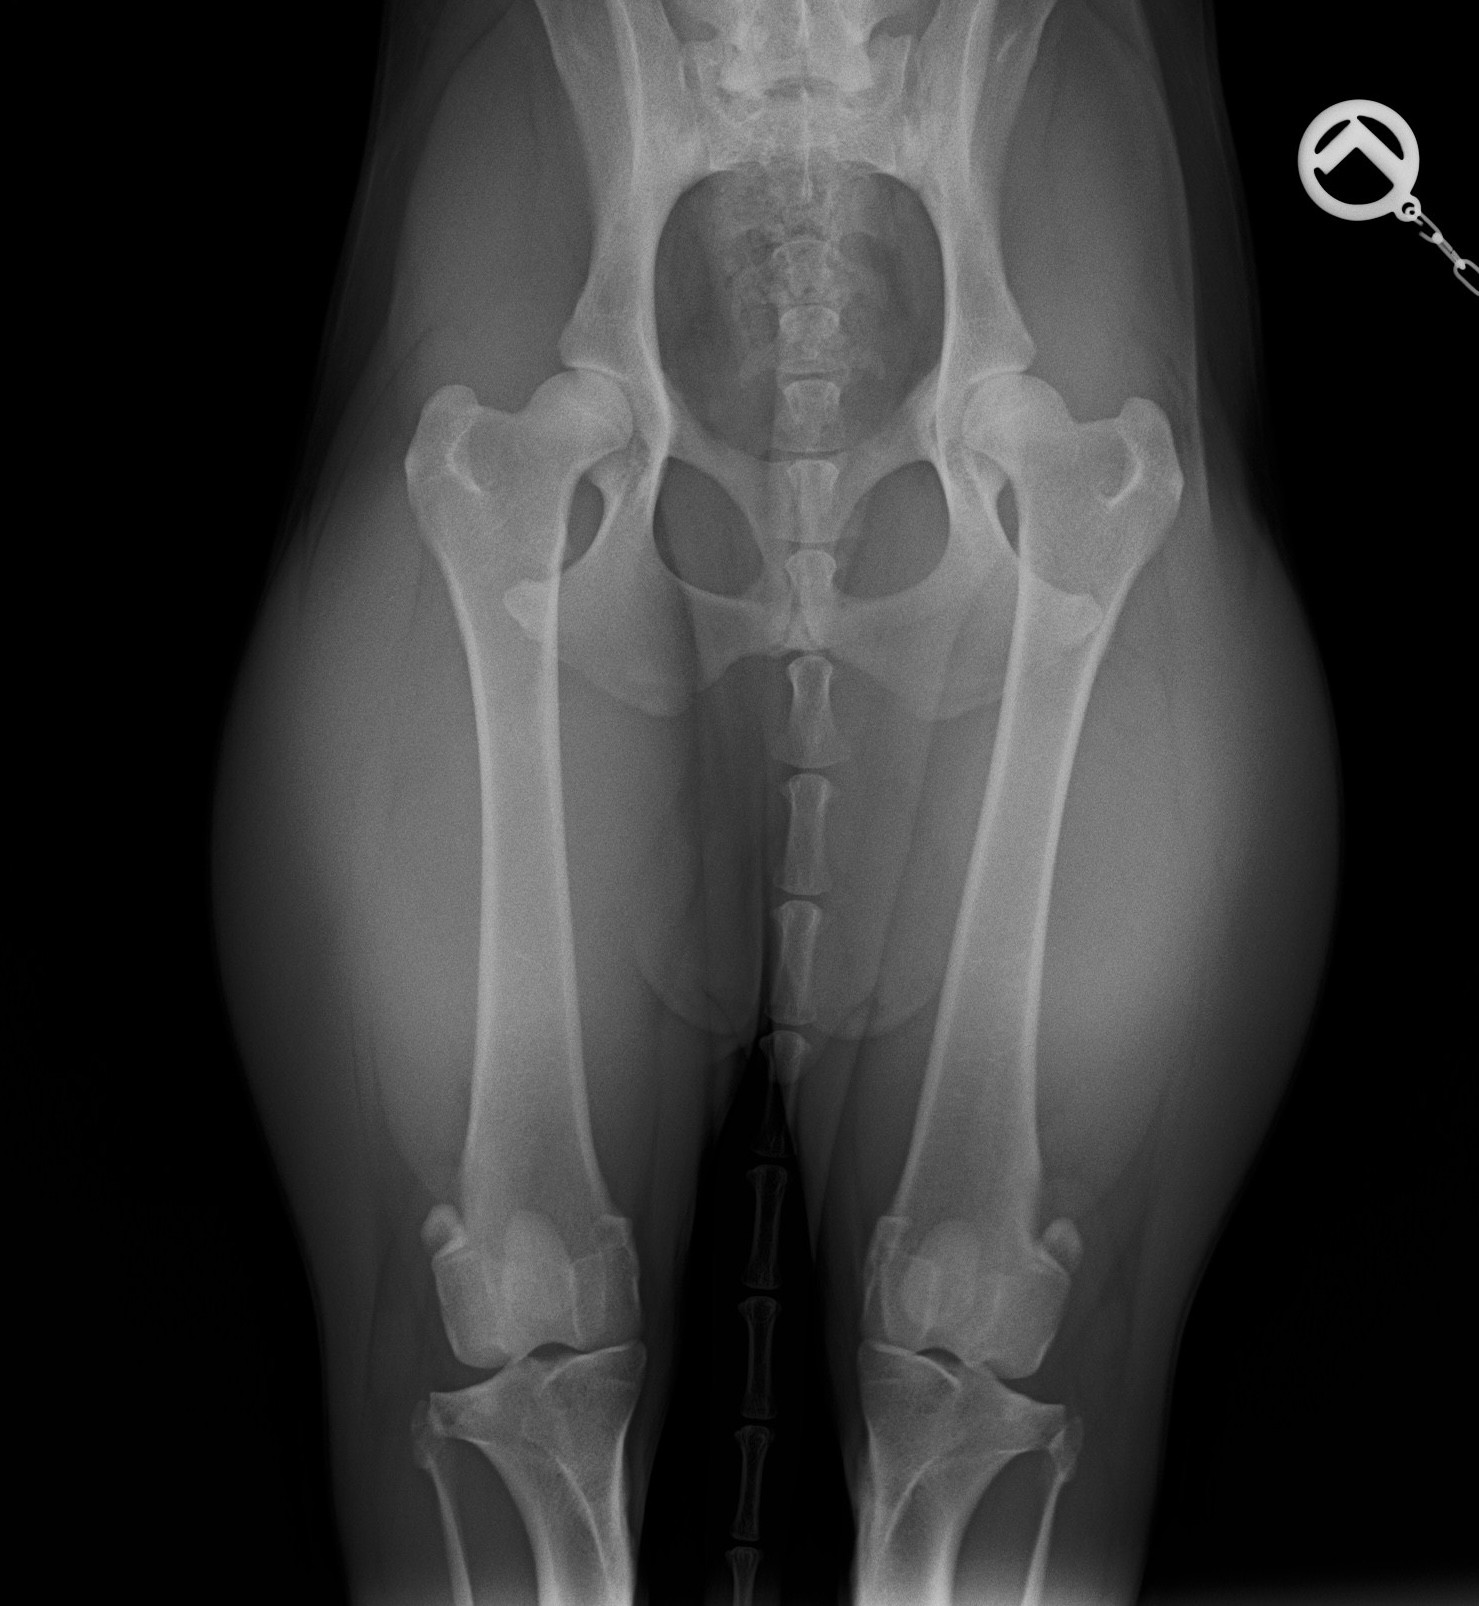

• bei Verschleißerscheinungen oder Fehlbildungen, z. B. HD, ED, Arthrose, Patellaluxation

Vor und nach der Operation gut begleitet

Gezielte physiotherapeutische Maßnahmen vor und nach einer OP können die Heilungsphase deutlich verkürzen und den Therapieerfolg langfristig sichern. Mögliche Einsatzbereiche sind z.B. Kreuzbandriss, Frakturen, Gelenkersatz, Patellaluxation,